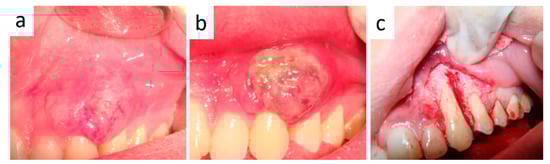

2. Case Presentation